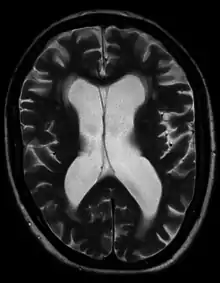

Hydrocephalus as seen on a CT scan of the brain. The black areas in the middle of the brain (the lateral ventricles) are abnormally large and filled with fluid.

Hydrocephalus ex vacuo from vascular dementia as seen on MRI